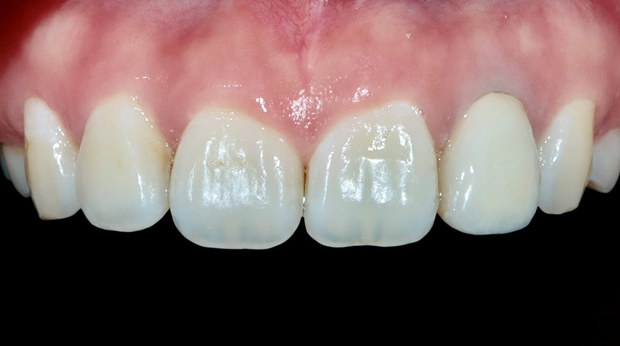

라미네이트